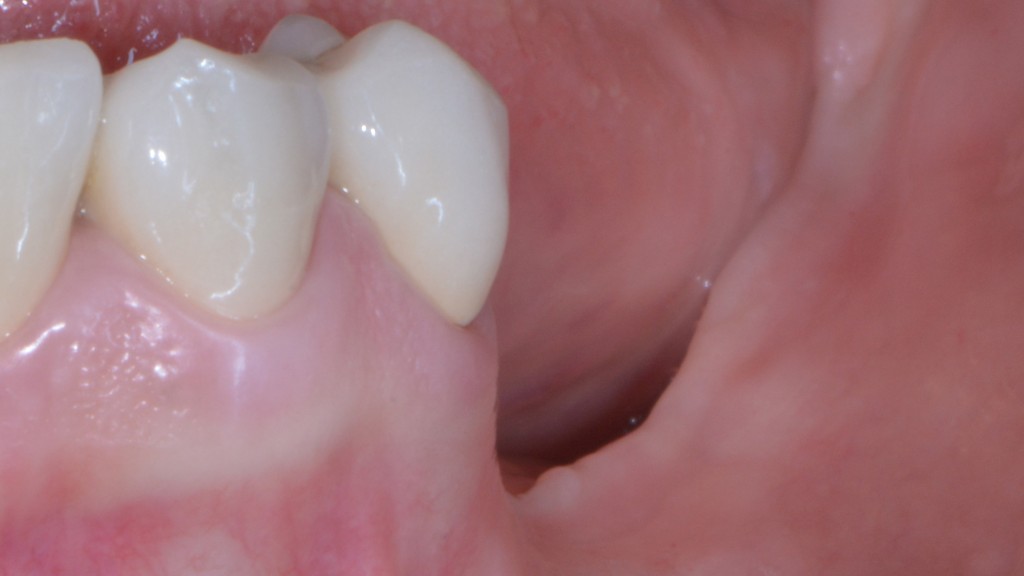

Prendiamo un caso quotidiano. Quello di Alessia che ha 33 anni:

DSC_3896

Puoi buttare giù due viti e metterci sopra due denti facendo una cosa molto lontana dalla natura.

O puoi riabilitare la paziente adeguatamente:

DSC_5588

Ma per fare questo non ci sono polverine magiche di osso di dinosauro o impianti di un millimetro. Ci sono anni di studio, sudore e  sangue (E SGUARONE!!) per noi… e un VAS 2 per la paziente!!!!!!! ?